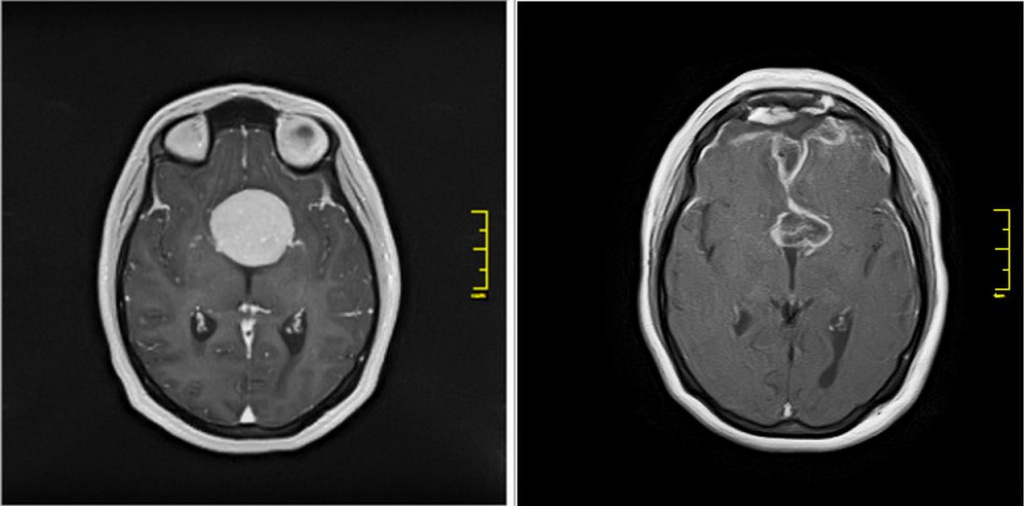

Операция по удалению крупной опухоли в голове прошла в новосибирском НИИИТО. Женщине был поставлен диагноз — менингиома турецкого седла, которая сдавливала и обрастала зрительные нервы и обе сонные артерии. Опухоль полностью разрушила левый зрительный нерв и нанесла поражение другим сосудам.

Микрохирургическое удаление менингиомы провел врач Вячеслав Ступак. В настоящее время пациентка была выписана, зрение женщины постепенно возвращается.